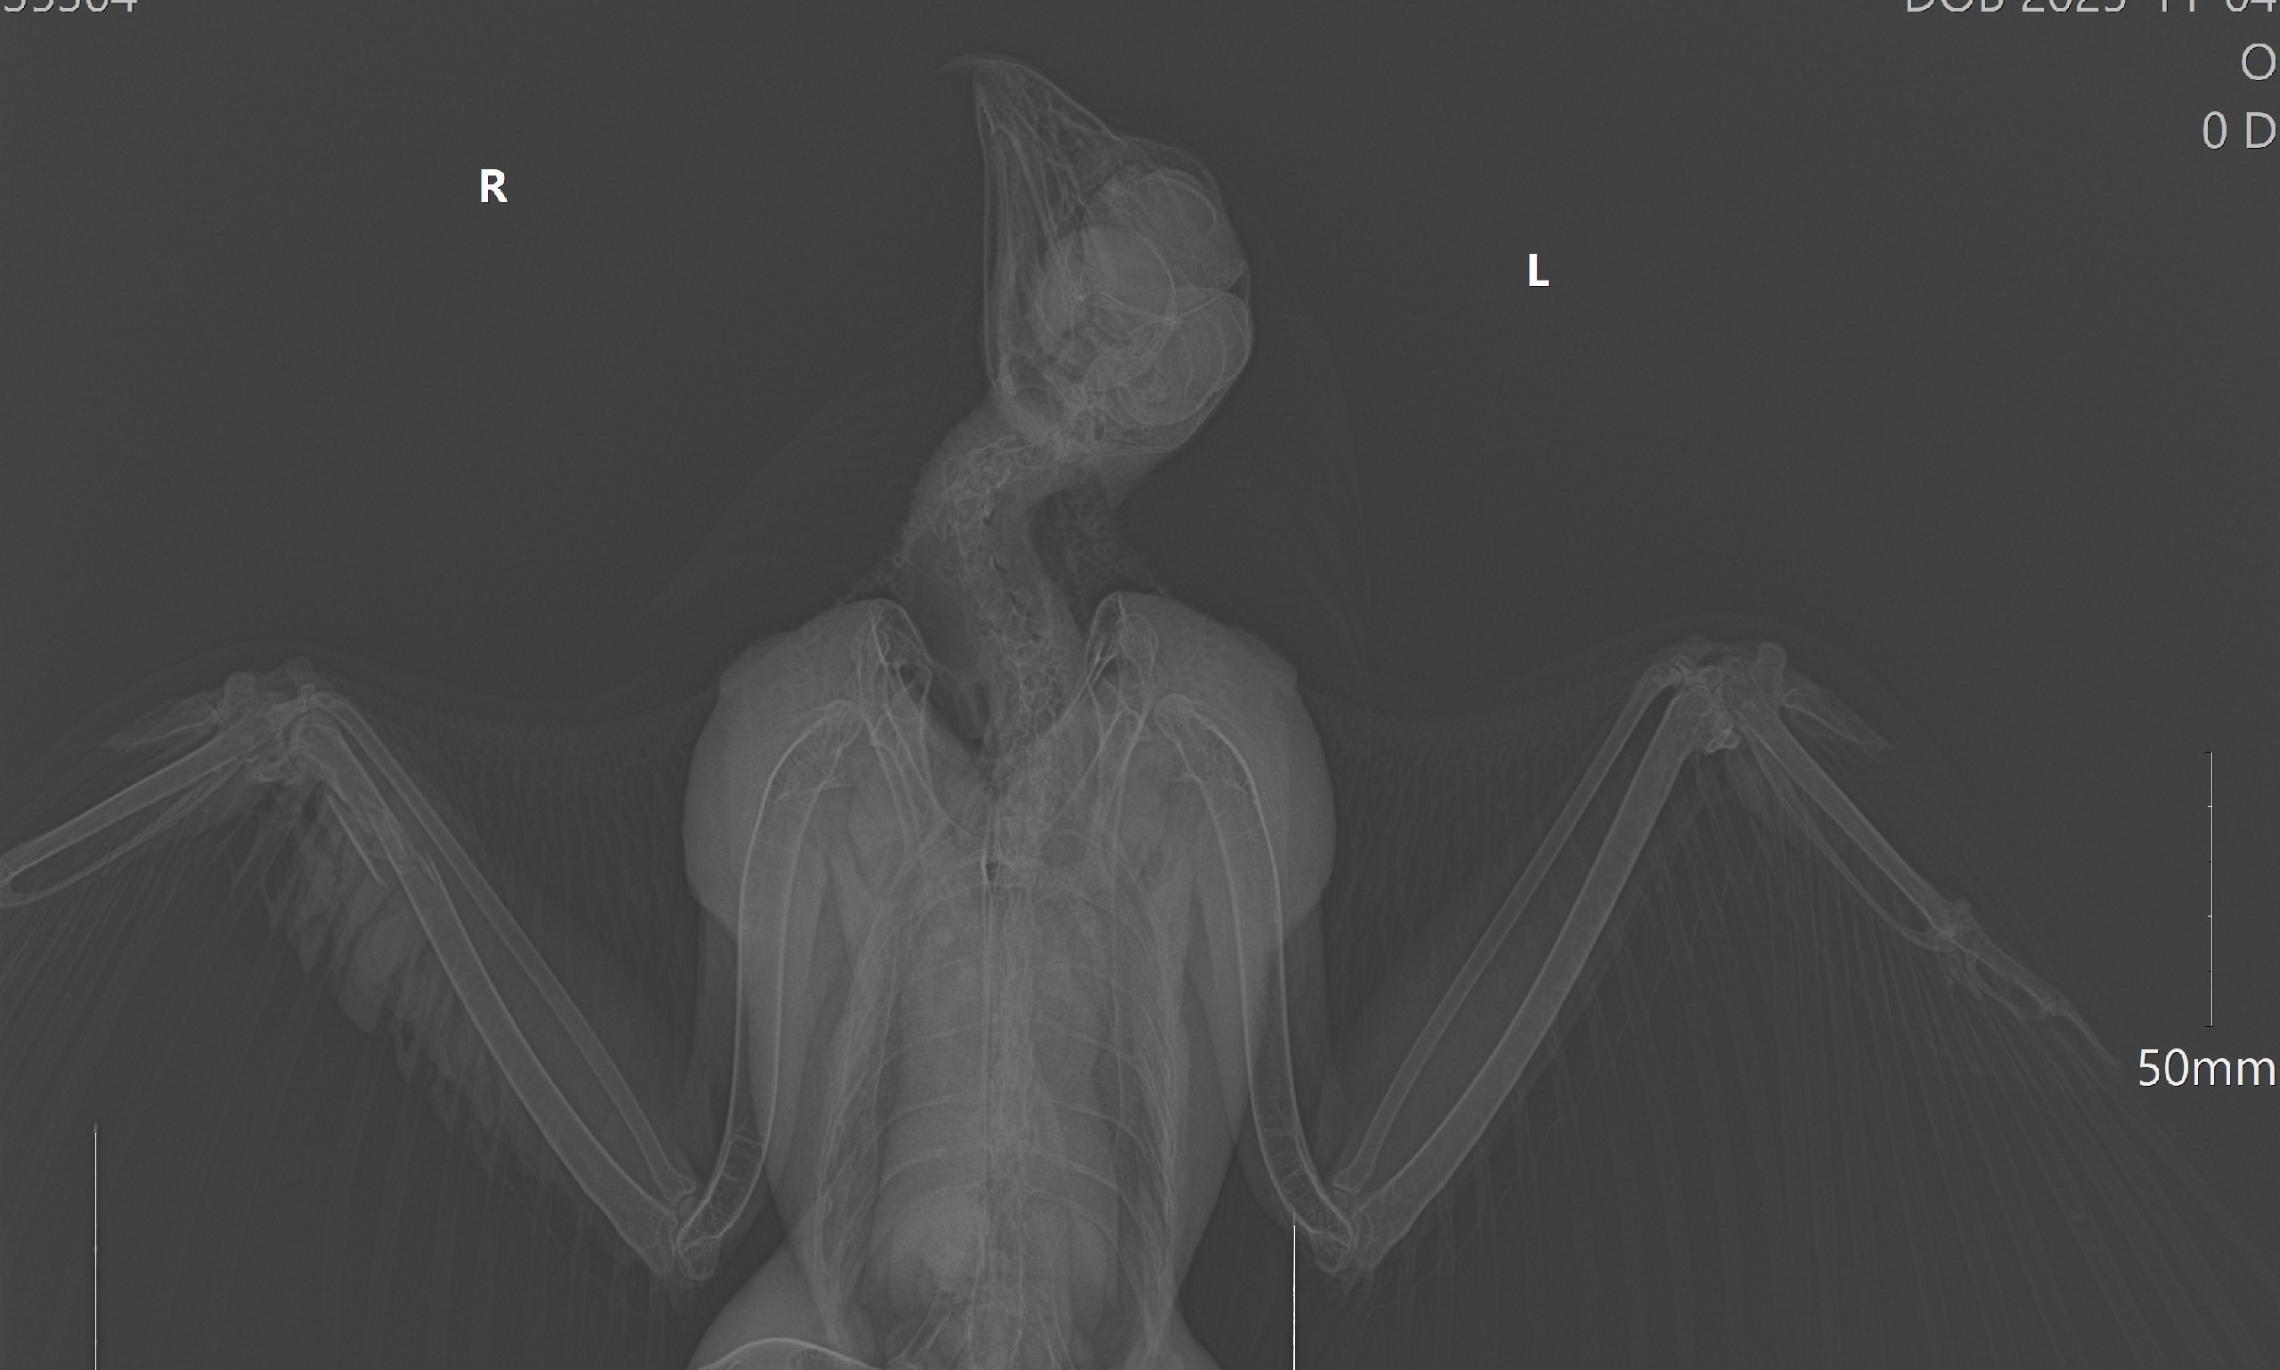

— Мы отвезли его на рентген. На снимке видно, что у птицы перелом правого крыла. Доктора сказали, что перелом не критичный, удачный и срастётся со временем сам. Никакой операции птичке делать не нужно. По какой причине возникла эта ситуация — история умалчивает, — рассказал Ирина Макарова.

Фото из соцсетей Ирины МакаровойФото из соцсетей Ирины Макаровой